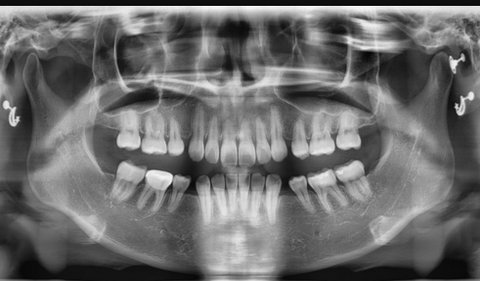

2. 이건 현재 ㅌㅁ치과에서 교정하고있는 피해자...

(첫번째사진이 교정전, 두번째사진이 2년 후임. 엑스레이도 교정 2년 후 사진..)

발치교정은 원래 투명교정으로 안되는 건데 ㅌㅁ치과 상담실장이 무작정 돈보고^^^ 투명교정 할수 있다고 해서 시작했는데 발치공간 안 줄어들어, 어금니 다 드러누워, 과개교합 생겨... 교정치과가 아니라 부작용치과임.